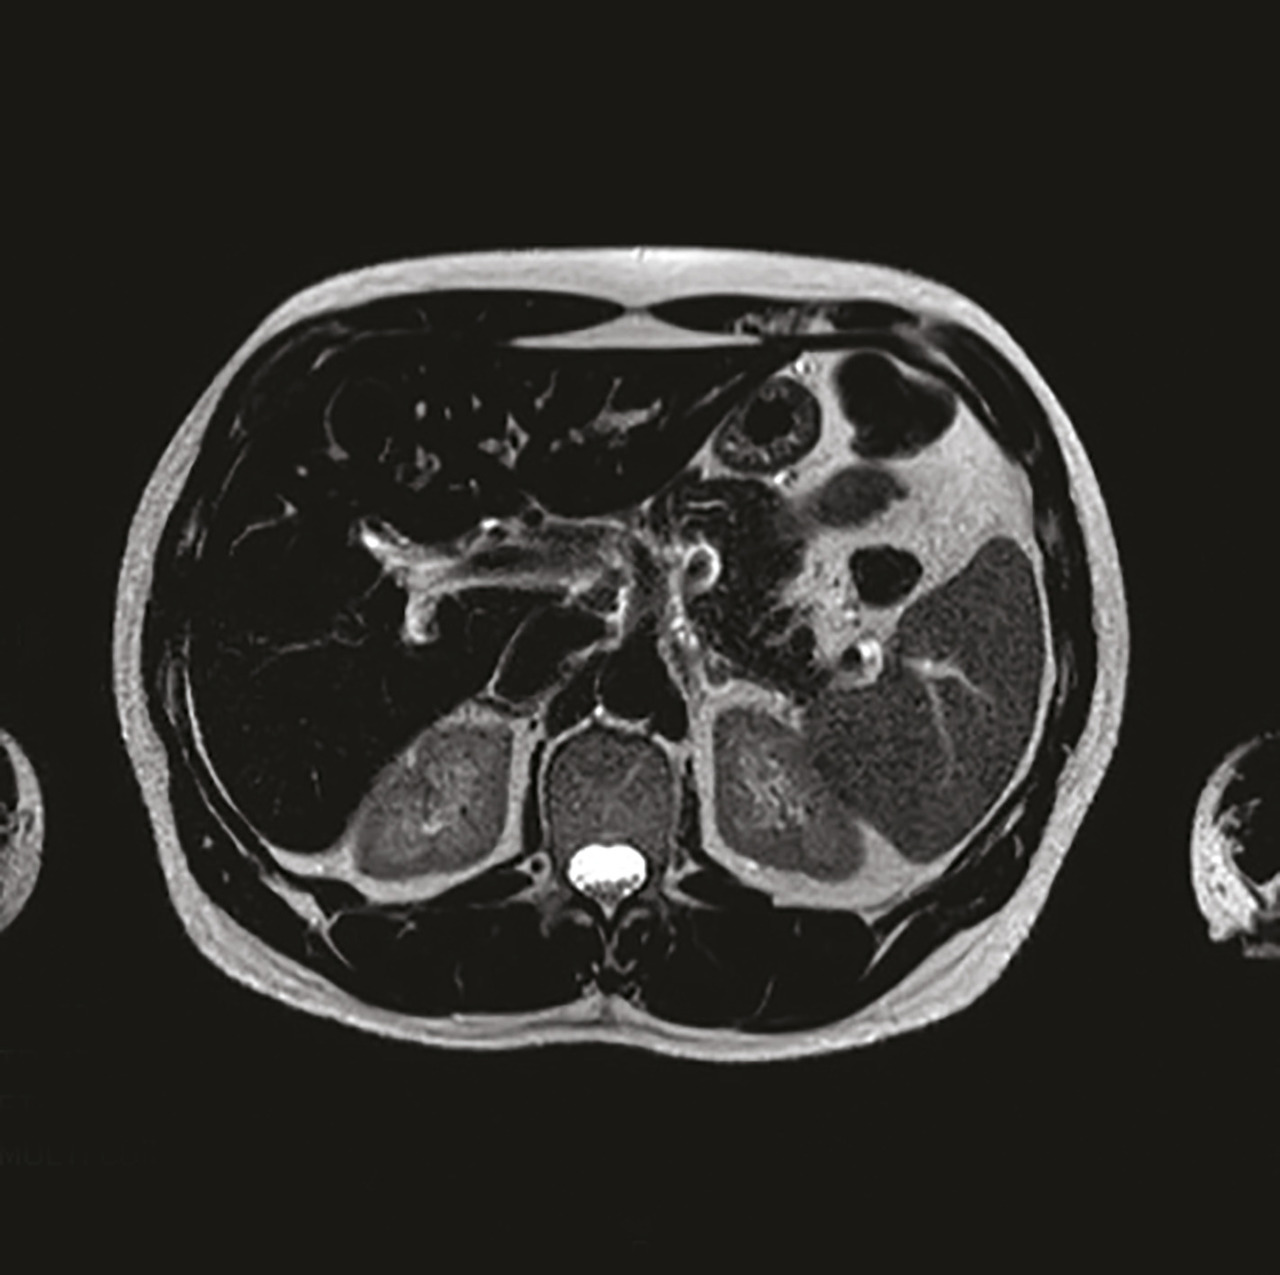

Cet homme de 53 ans suivi pour un syndrome anxiodépressif et un alcoolisme sevré, consultait pour une asthénie et un « burn-out ». L’interrogatoire notait que la fatigue s’estompait les week-ends et durant les vacances, et ne rapportait pas d’autre plainte fonctionnelle. Une biologie antérieure montrait une cytolyse hépatique prédominant sur les alanine aminotransférases (1,5 fois la valeur normale). Dans ce contexte, un bilan systématique était prescrit avec un contrôle thyroïdien et ferrique, montrant une hyperferritinémie à 3 756 µg/L. Le bilan complémentaire notait un coefficient de saturation de la transferrine (CST) à 90 %, une surcharge ferrique hépatique en imagerie par résonance magnétique (IRM, fig. 1 et 2 ) à 392 µmol/g, et une mutation postive C282Y homozygote. Le diagnostic d’hémochromatose héréditaire a été annoncé au patient au cours d’une consultation dédiée, en lui expliquant la nécessité d’une saignée hebdomadaire avec comme objectif une ferritinémie inférieure à 50 µg/L et l’intérêt d’un dépistage familial. L’évolution est marquée par une stabilisation de l’asthénie permettant à ce patient sportif une reprise partielle de ses activités physiques.

L’asthénie est un motif fréquent de consultation en médecine générale.1 Il n’existe pas de recommandations pour un bilan type. Un examen clinique précis vise à ne proposer un bilan qu’aux patients suspects d’une maladie sous-jacente, tels que notre patient ayant une anomalie du bilan hépatique. L’hémochromatose liée au gène HFE (type 1)2 est une maladie génétique de surcharge en fer (mutation C282Y). Le retard diagnostique est fréquent, devant des symptômes peu spécifiques, mais un diagnostic précoce permet de mieux prévenir les complications. Le CST et l’IRM sont les examens de référence. Les facteurs de risque de survenue d’une complication sont la consommation d’alcool et les viroses hépatotropes. Le traitement repose sur des saignées.